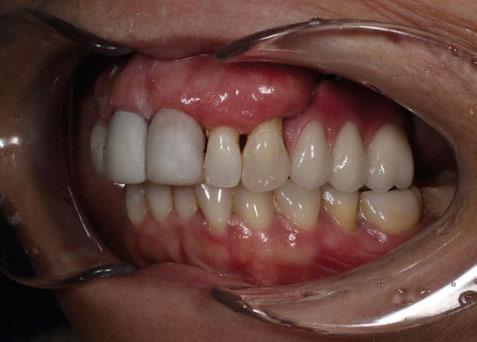

A partir del estudio radiológico y de las imágenes fotográficas podemos observar edentulismo de 17, 15, 14, 12,

Figura 1a. Foto intraoral frontal inicial.

Figura 1b. Foto intraoral lateral izquierda inicial.

Figura 1c. Foto intraoral lateral derecha inicial.

25, 26, 28, 37, 38, 47 y 48. Presentaba corona desajustada en 13 con extensión en 12, implantes en 35-36, 45-46, con coronas ferulizadas en 35-36, 45-46, y dientes anteriores superiores con enfermedad periodontal Grado IV.

2. Exploración de tejidos blandos

El paciente presentaba biotipo periodontal grueso, con márgenes asimétricos, con recesiones gingivales a nivel de 11 y 13 y pérdida de tejidos blandos interproximales.

3. Exploración de tejidos duros

En la exploración radiográfica (OPG, CBCT) observamos la existencia de pérdida ósea interproximal, lesión apical a nivel de la raíz mesial del 27 y el cordal del primer cuadrante incluido y neumatización sinusal del primer y segundo cuadrante.

En el CBCT observamos pérdida ósea posterior superior debida a la neumatización de los senos maxilares izquierdo y derecho. También podemos observar disponibilidad ósea apical suficiente en dientes antero-superiores para la realización de una Implantología inmediata y corticales vestibulares y palatinas conservadas.